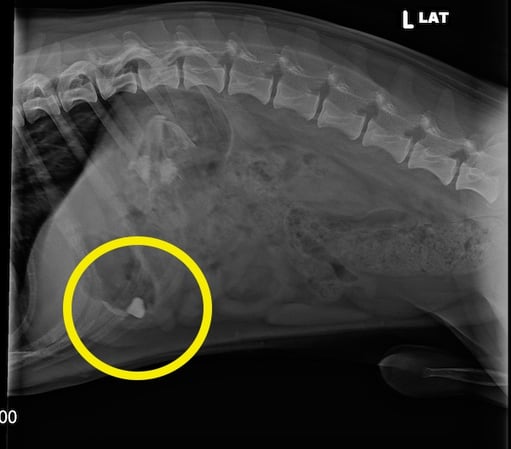

I found out my dog, Fozzie, had swallowed a rock when I took him in for X-rays after he also swallowed a larger animal bone that was under our deck (a story for another day). Fortunately, the rock was smooth and small enough to pass without causing any issues – check out his X-ray below. But even when things turn out okay, they could just as easily go very wrong.